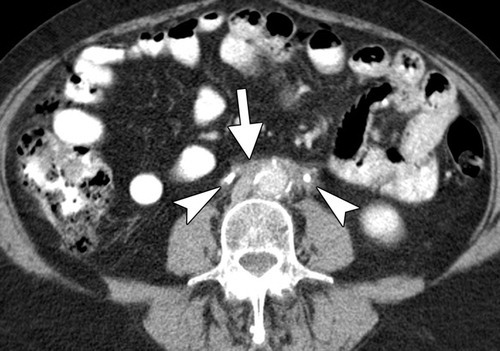

retroperitoneal fibrosis